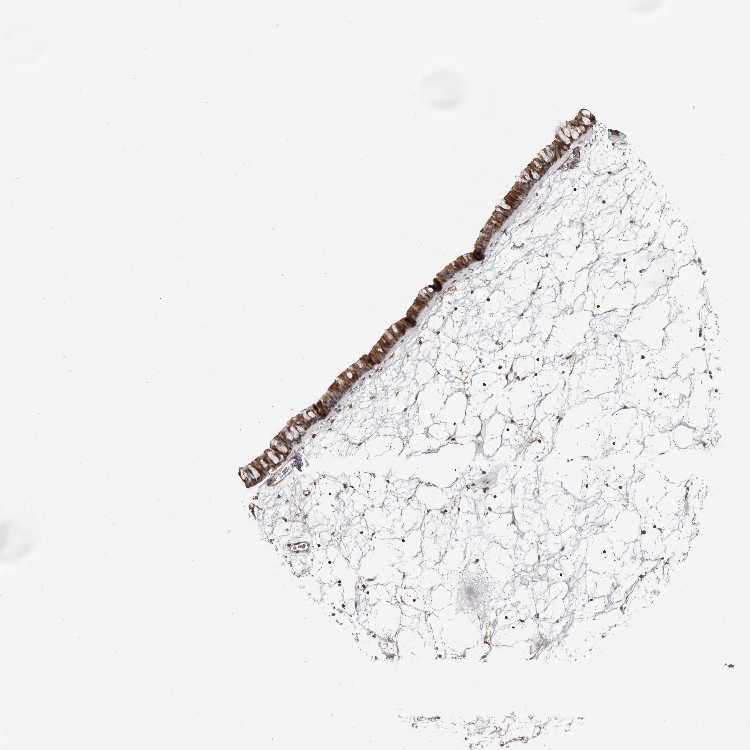

TISSUE PRIMARY DATA NASOPHARYNX Show tissue menu

NASOPHARYNX - Antibody stainingi

Antibody staining in the annotated cell types in the current human tissue is reported as not detected, low, medium, or high, based on conventional immunohistochemistry profiling in selected tissues. This score is based on the combination of the staining intensity and fraction of stained cells.

Each image is clickable and will lead to virtual microscopy that enables deeper exploration of all samples and also displays staining intensity scores, fraction scores and subcellular localization as well as patient and tissue information for each sample.

Antibody HPA027481Antibody HPA028722

Respiratory epithelial cells HighHigh